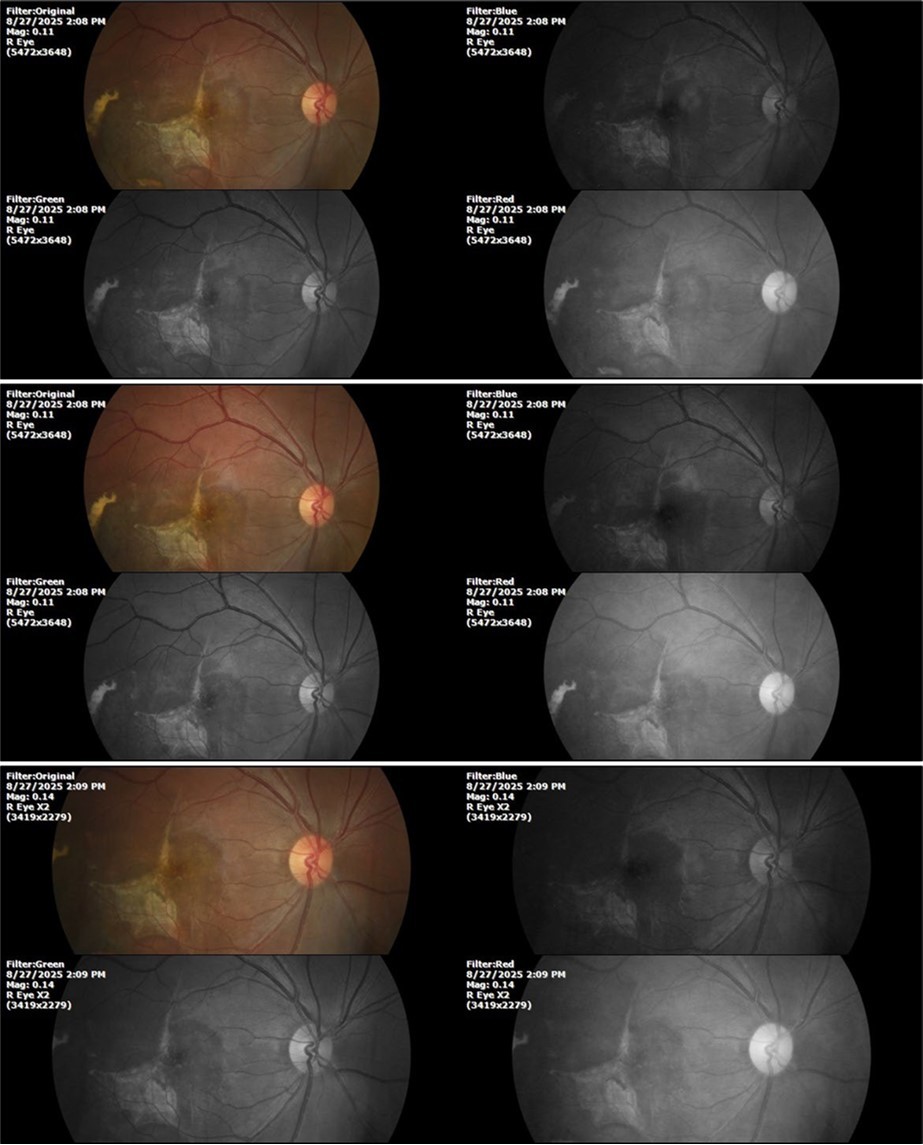

August 26, 2025

It's been fine, there's only a little veil that prevents it from seeing well completely, although it's very transparent (Figure 31, Figure 32, Figure 33, Figure 34, Figure 35, Figure 36).

Figure 31.The photograph of the right eye shows an almost normal mirror reflection, as well as a better pupillary dilation.

Figure 32.The macro photograph of the right eye shows us a cornea, anterior camera, and crystalline lens in very good condition.

Figure 33.The 3 previous photographs show that whitish mass has almost completely disappeared, and to date only a remnant remains on the left side of the photograph. The chorioretinal scar that is now observed corresponds to the area affected by the blunt trauma, which presumably caused rupture of Bruch's membrane. Fortunately, the macular region has recovered almost in its entirety, so the impairment in central vision was minimal.

Figure 8.The photograph of the superior temporal region of the retina of the right eye shows the extent of subretinal bleeding as well as retinal edema.

Figure 9.The extent of bleeding, mainly subretinal, is extensive and of significant volume, suggesting choroid rupture in this area.

Figure 10.The location of the bleeding is mainly subretinal, although blood is seen in minimal quantity in the vitreous body.